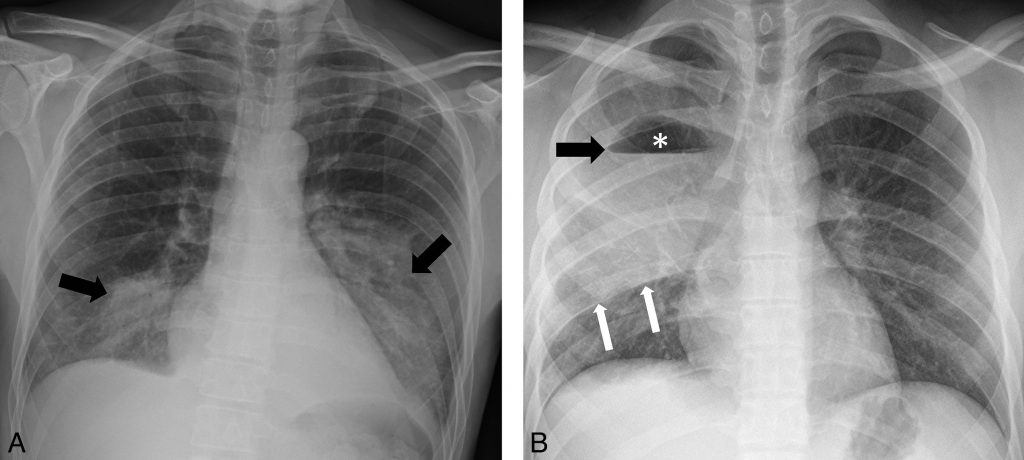

La présence d’une atteinte bilatérale ou multilobaire en radiographie de thorax ou encore une extension rapide sur deux radiographies proches constituent des signes de gravité (figure 96.2).

Fig. 96.2. Radiographie de thorax de face.

A Pneumonie bilatérale se traduisant par des foyers de condensations alvéolaires du lobe inférieur droit et du lobe inférieur gauche, n’effaçant pas la silhouette cardiaque (flèches). B Pneumonie lobaire supérieure droite se traduisant par un foyer de condensation alvéolaire du lobe supérieur droit avec appui scissural (flèches blanches), siège d’une excavation : clarté aérique supérieure (astérisque), niveau hydroaérique horizontal (flèche noire).

Source : CERF, CNEBMN, 2022.